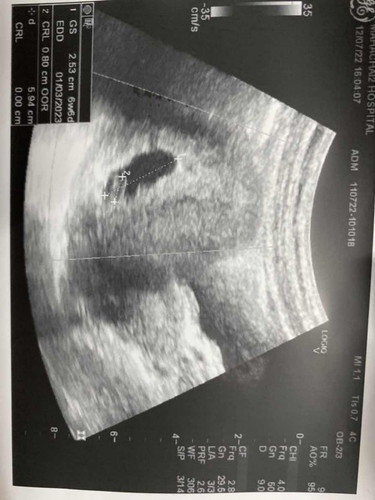

ท้อง7วีค ปวดท้องเหมือนปวดอึแต่ไปเข้าห้องน้ำแล้วมีเลือด แล้วก็หยุดเลือกเป็นสีน้ำตาล ไปหาหมอหมอบอกเจอตัวเด็กแต่หัวใจน้องไม่เต้น

หมอแนะนำให้ขูดมดลูกแต่เราไม่ขูด #ท้องแรกคะ #ขอคำแนะนำหน่อยค่ะ

วันนี้ก็ไปหาบอกอีกรอบเพราะยังมีเลือดไหลอยู่หมอซาวผ่านกล้องดูน้องก็ยังอยู่แล้วบอกรอผลอาทิตย์หน้า ยังมีหวังอยู่ใช่ไหมคะ

ถ้าหมอแนะนำขูดมดลูกคือน้องไปแล้วนะคะแม่ แต่แม่รออีกสัก2สัปดาห์ก็ได้ค่ะแล้วไปให้หมออัลตร่าซาวน์อีกรอบเผื่อน้องยังอยู่